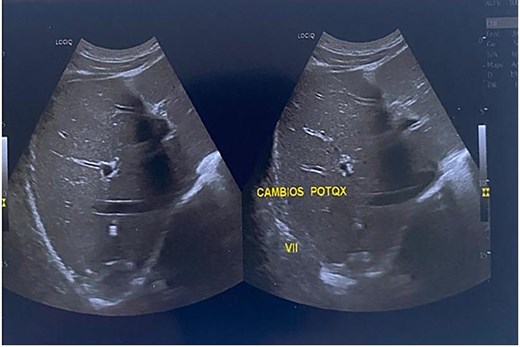

The patient had an uncomplicated recovery and was discharged on postoperative day two with no evidence of bile leakage. Three cycles of albendazole were prescribed (at intervals of 28 days with 14-day drug-free periods). The drain was removed after 15 days; no biliary fistula or residual fluid collection was detected. Follow-up ultrasound at three months showed no recurrence (Fig. 5).

Three-month follow-up ultrasound showing small linear echogenic areas in segment VII, consistent with postsurgical changes. No anechoic or recurrent cystic areas were observed.